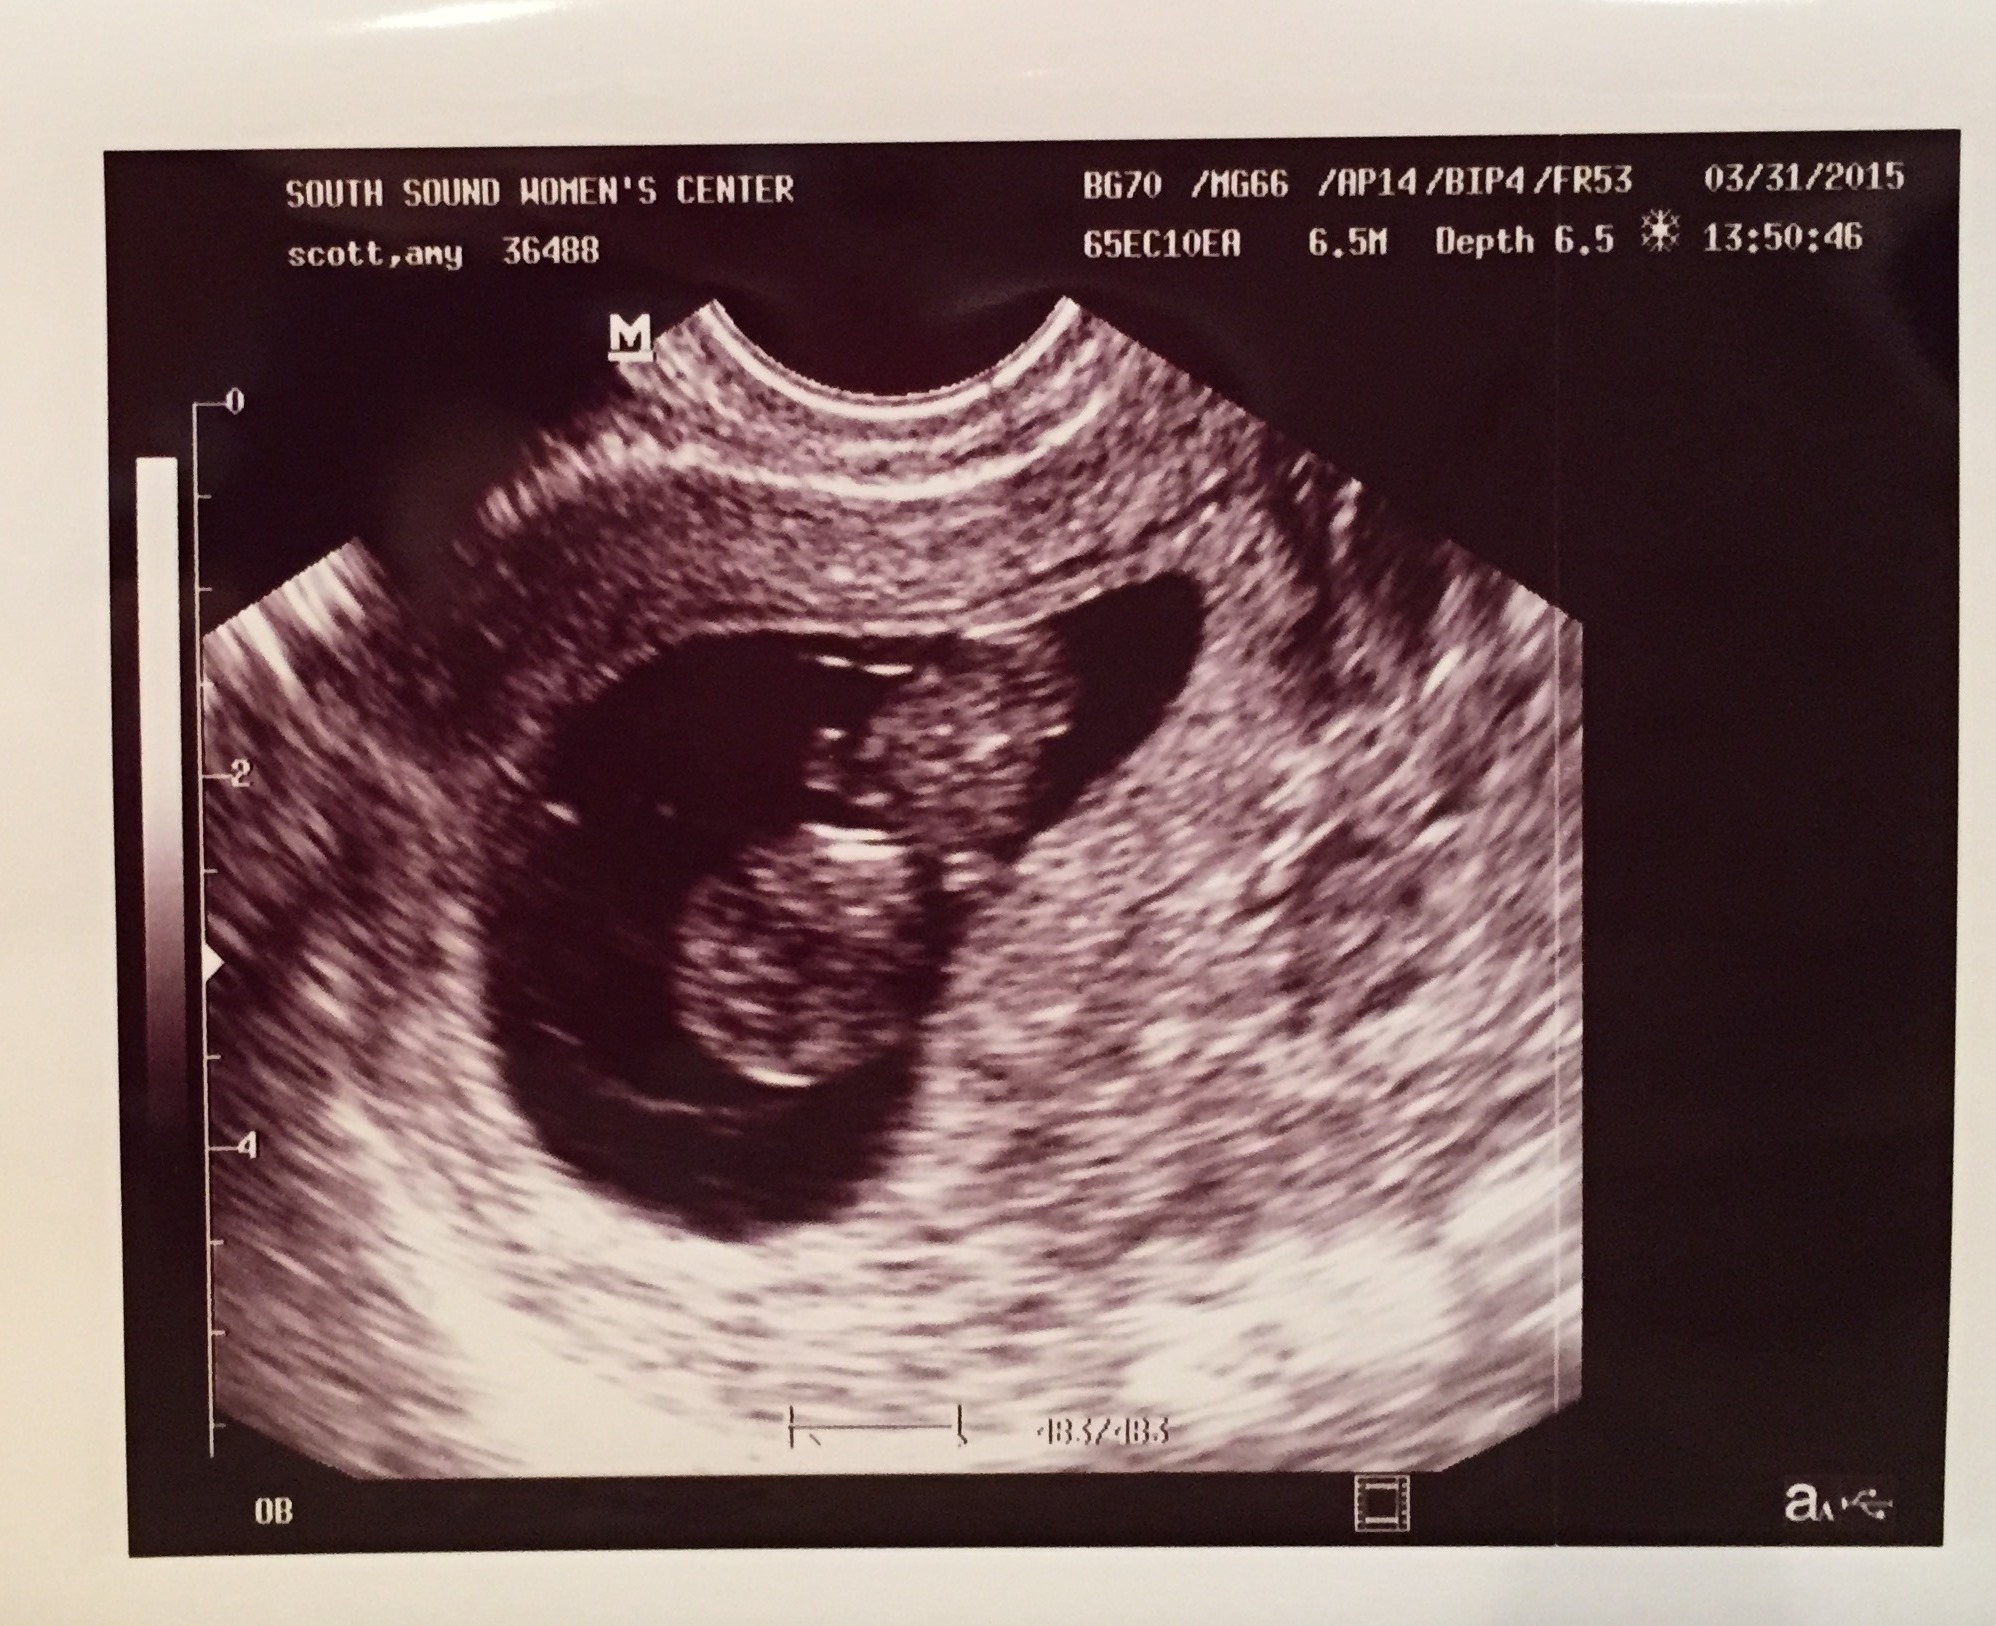

I’m 10 weeks along, almost 11. My plan wasn’t really to make this news public until Easter, but… My hubby got a bit carried away and started telling people, so I figured, why not get it out in the open. We had our first ultrasound onTuesday and the baby is healthy and happy. I figured once I saw that all was good then we could let the world know. Making a big public announcement is hard for me. I liked keeping this pregnancy a secret because it meant that people would treat me normally for a little while longer. When it comes down to it, people are going to know soon anyway. Why prolong the wait? I’m amazed at how big I feel already. I know they say that happens with subsequent pregnancies. It still caught me a bit off guard. I might have break out the fat pants sooner rather than later!